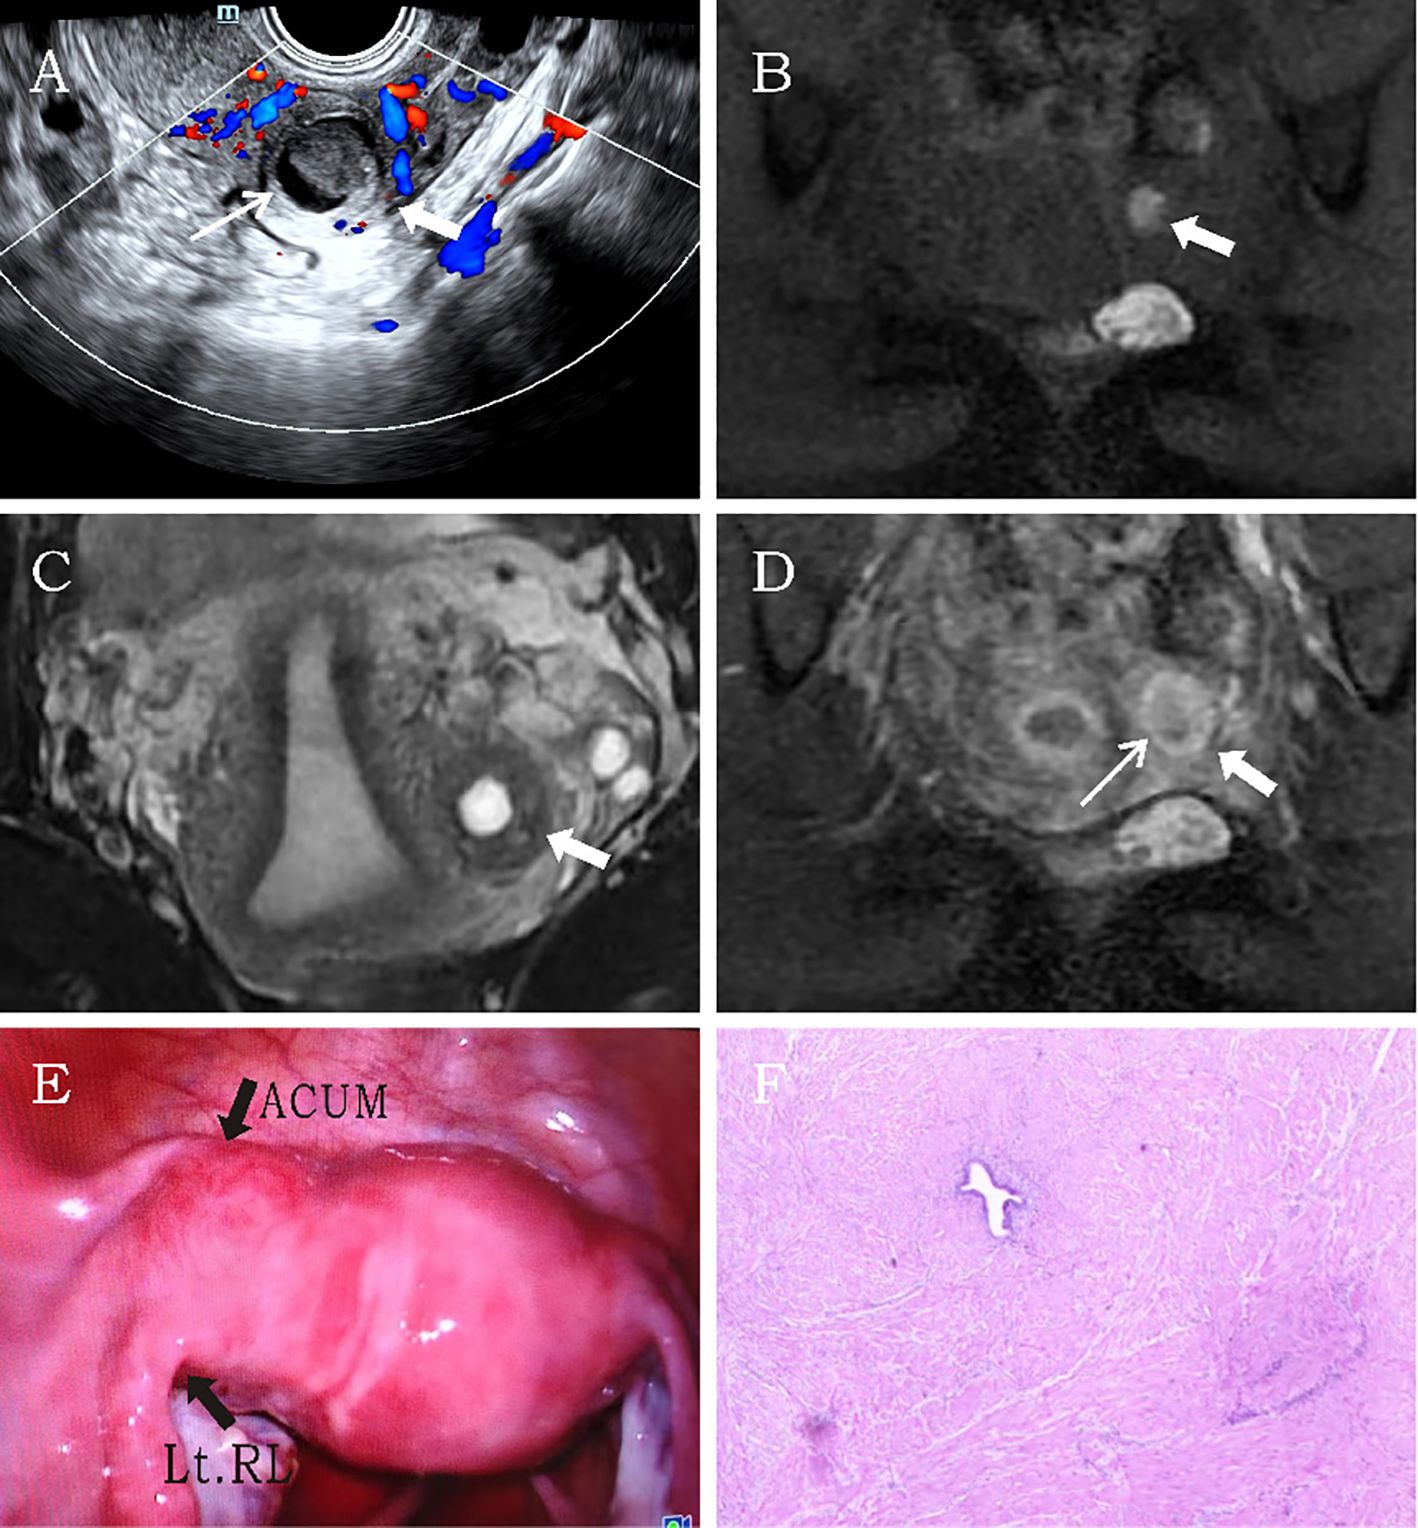

A 34-year-old married woman (gravida 2 para 2) was admitted due to intermittent lower abdominal pain for over 1 month. The patient had a history of mild dysmenorrhea. She experienced severe pain in the left lower abdomen 1 month earlier. She was diagnosed with acute pelvic inflammatory disease by external ultrasound examination, which revealed a heterogeneous echogenic mass within the left uterine myometrium. The pain resolved after anti-inflammatory and antispasmodic treatments. However, the patient experienced a recurrence of left lower abdominal pain 1 day ago, characterized by persistent colicky pain that was unresponsive to medication therapy. The patient had no contributory medical or family history. Physical examination revealed mild protrusion of the left anterior uterine wall without tenderness. All laboratory findings were within the normal limits. Ultrasonography demonstrated a well-circumscribed, regularly shaped thick-walled cystic mass (29 × 30 × 31 mm) in the left uterine wall. The lesion contained a cystic cavity (17 × 14 × 18 mm) with ground-glass echogenicity and a solid medium-echo component (13 × 12 × 15 mm). The cystic lumen was lined by a 1.3-mm-thick circumferential endometrial layer and surrounded by a 5.1-mm-thick hypoechoic myometrial rim. The uterine cavity appeared normal with unremarkable bilateral ovaries. CDFI revealed a circular blood flow signal surrounding the cystic mass (Figure 3A). The imaging characteristics confirmed a diagnosis of ACUM. MRI revealed a round abnormal signal intensity lesion within the left broad ligament of the uterine myometrium. The lesion demonstrated central hyperintensity with slightly hypointense margins containing scattered punctate hyperintense foci on both T1WI and T2WI (Figures 3B, C). Contrast-enhanced imaging showed no significant central enhancement (Figure 3D). These MRI features were suggestive of ACUM. The patient was diagnosed with ACUM by laparoscopic surgery (Figures 3E, F) and underwent ACUM excision. The patient remained asymptomatic with no recurrence during the 6-month postoperative follow-up period.

Figure 3. Representative image of clinical data for the third case. (A) Transvaginal ultrasound demonstrates a thick-walled cystic mass (thick white arrow) within the left lateral myometrium, showing a thin endometrial-like lining (thin white arrow) along the cavity wall. The remaining uterine architecture appears unremarkable. (B–D) MRI reveals an abnormal signal focus (thick white arrow) in the left myometrial wall. The lesion exhibits central hyperintensity on both T1- and T2-weighted images. Post-contrast imaging displays thin rim-like enhancement (thin white arrow) along the cavity wall, while T2-weighted imaging shows a hypointense rim surrounding the cavity, consistent with myometrial signal characteristics. (E) Laparoscopic visualization identifies a protruding mass at the uterine round ligament insertion site. (F) Histopathological examination (H&E, ×10). The specimen consists of smooth muscle tissue partially lined by hyperplastic endometrium, with interspersed endometrial glands and stroma within the muscular wall.